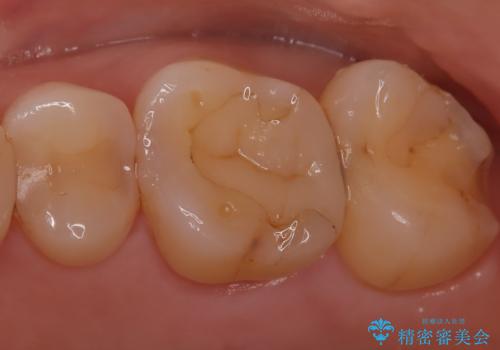

【セラミックインレー】適合の良いセラミックインレーを入れたい。

- 毎回フロスが引っかかることを気にされており、改善のため適合の良いセラミックインレーで修復しました。

以前に他院で詰め物をいれた時は、フロスが毎回ちぎれて大変だったそうですが改善して喜んでおられました。

当院のセラミックインレーは必ずラバーダムを使用して接着しています。